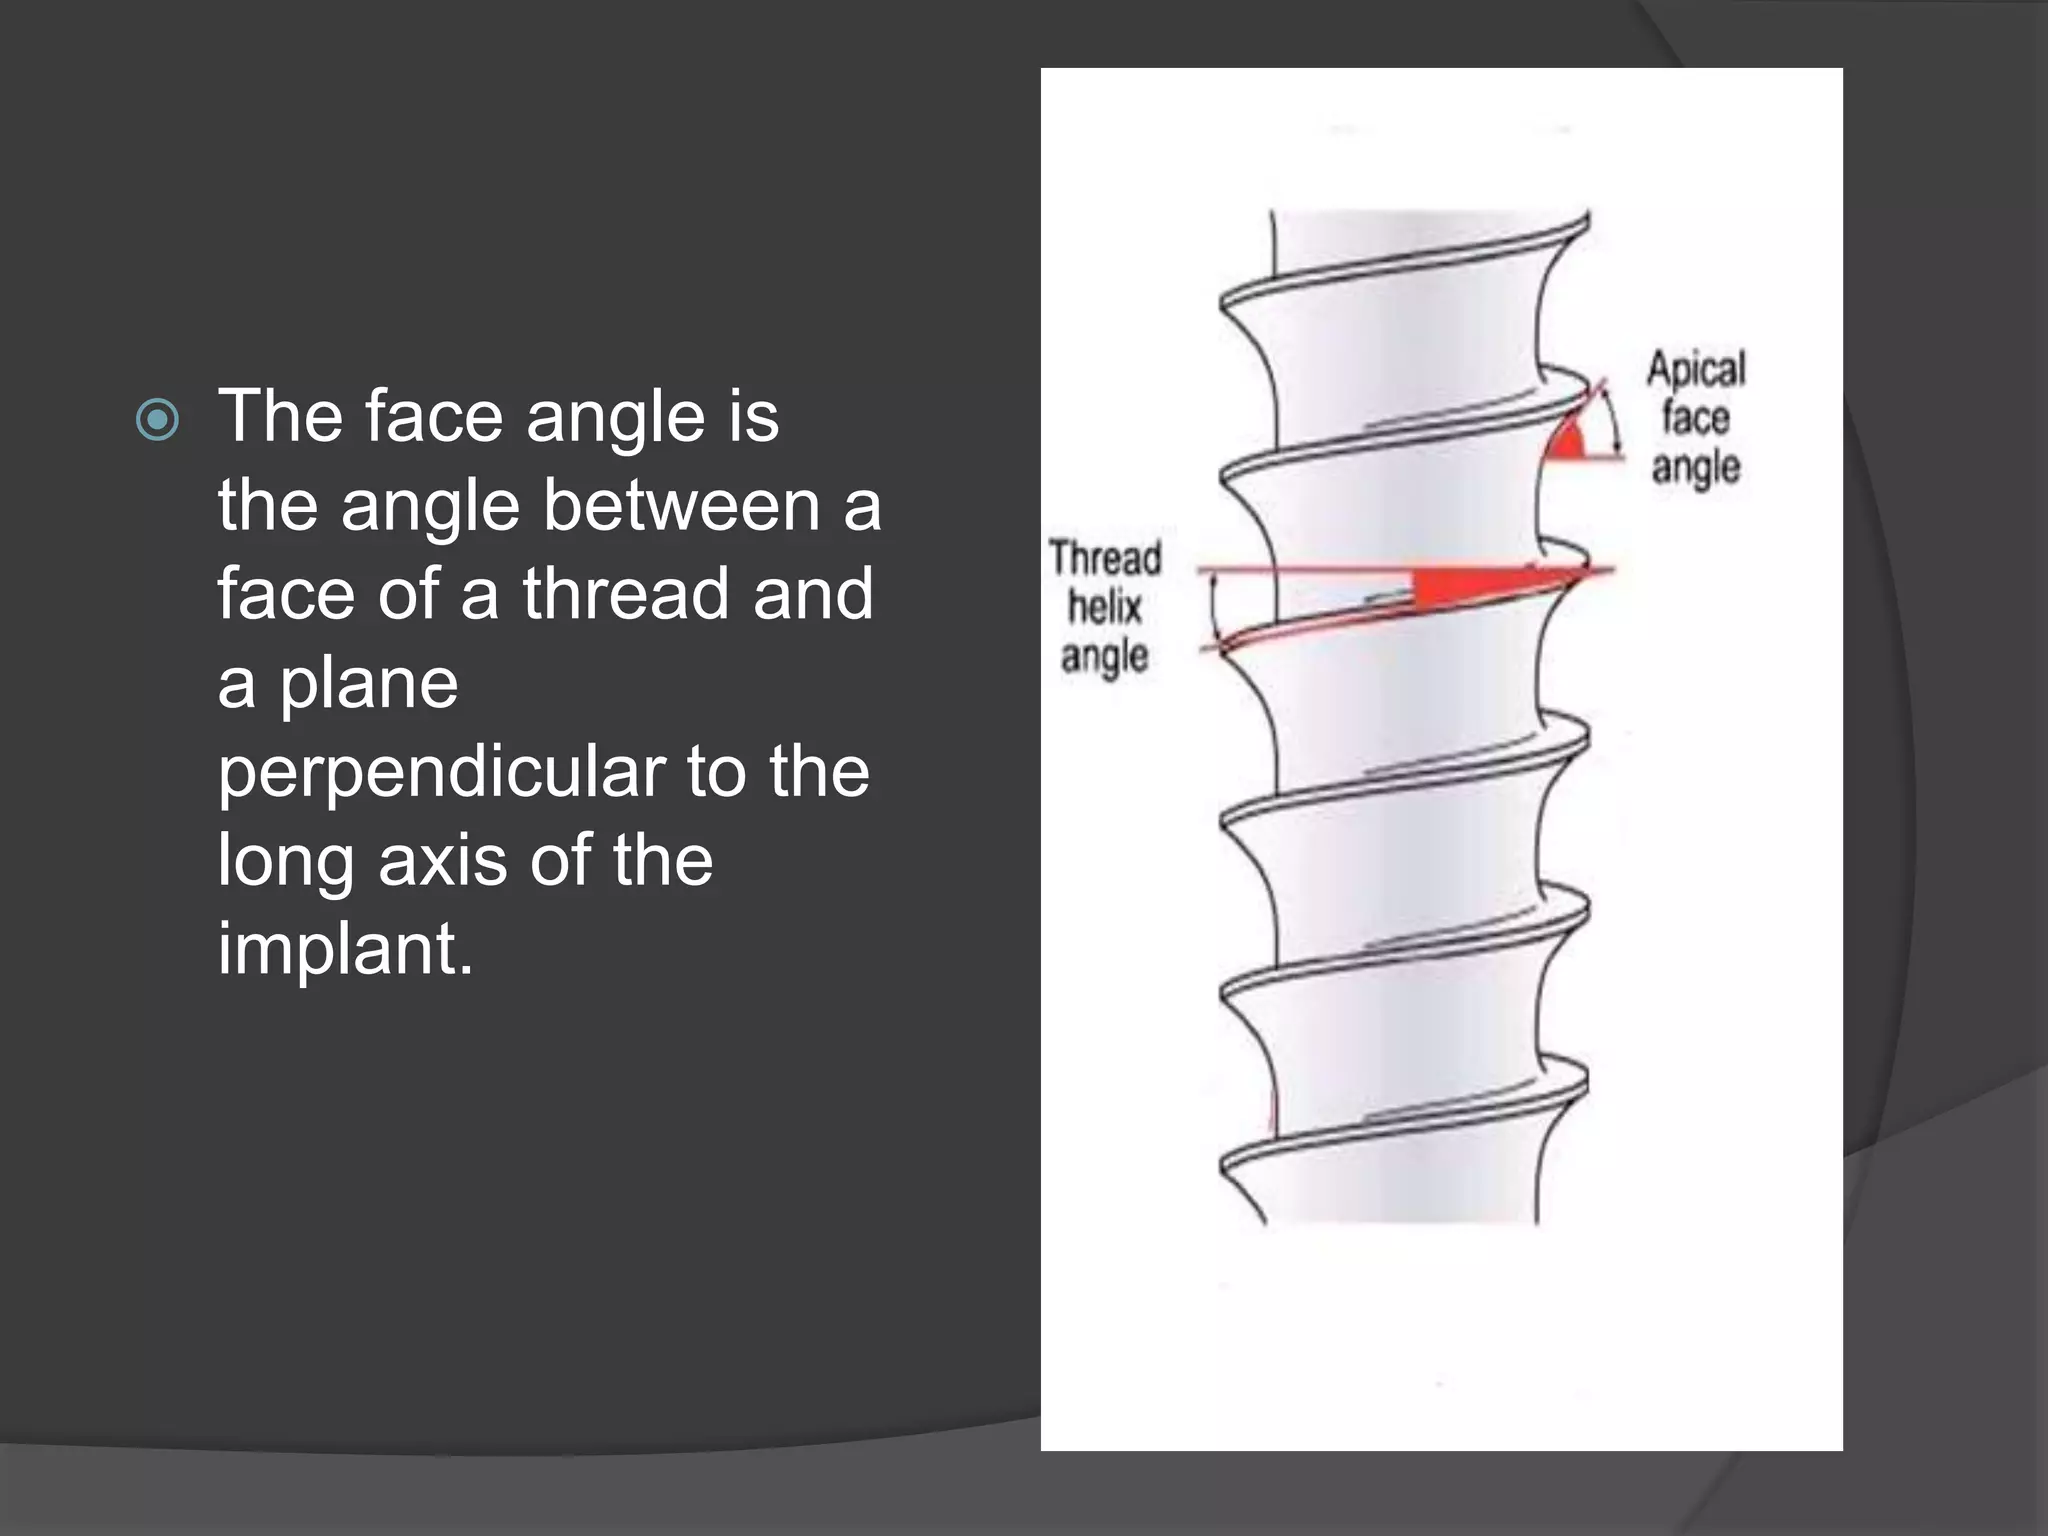

This document discusses factors that influence osseointegration and primary stability of dental implants, including implant design characteristics, surgical technique, and loading protocols. Specifically, it covers the processes of osseointegration and how forces on implants can either promote or inhibit bone remodeling. Key implant design considerations like length, diameter, threads, coatings and surface topography are analyzed in terms of their effects on stress distribution and bone-implant contact. The importance of primary stability and factors influencing it like bone quality and surgical skill are also addressed. Loading protocols ranging from immediate to conventional loading are compared.